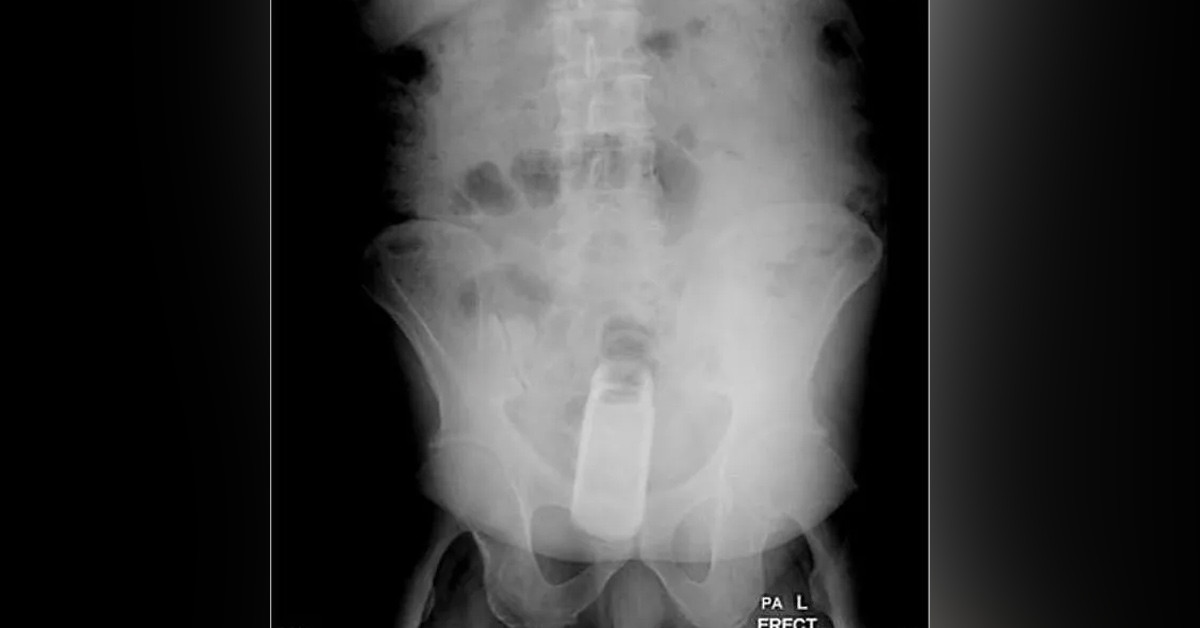

İranlı adamın bütün derdi, çektirdiği röntgen filmlerinin çıkmasıyla doktorlar tarafından anlaşıldı.

Doktorlar detaylı bir incelemenin sonucunda adamın makatında 12 santimetre boyutunda bir pet şişe buldu.

Genel anestezi uygulanan adamın makat bölgesi yırtılmadan ve kanama olmadan makatındaki şişe çıkarıldı.